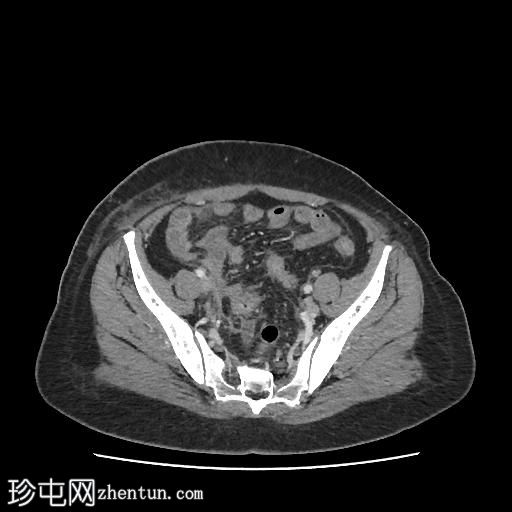

轴位肾盂排泄期

CT扫描显示:

左侧膀胱后外侧壁完全撕裂,造影剂外渗至盆腔

盆腔内可见少量积液

腹膜脂肪条索状改变,腹膜反折增厚强化,提示盆腔腹膜炎